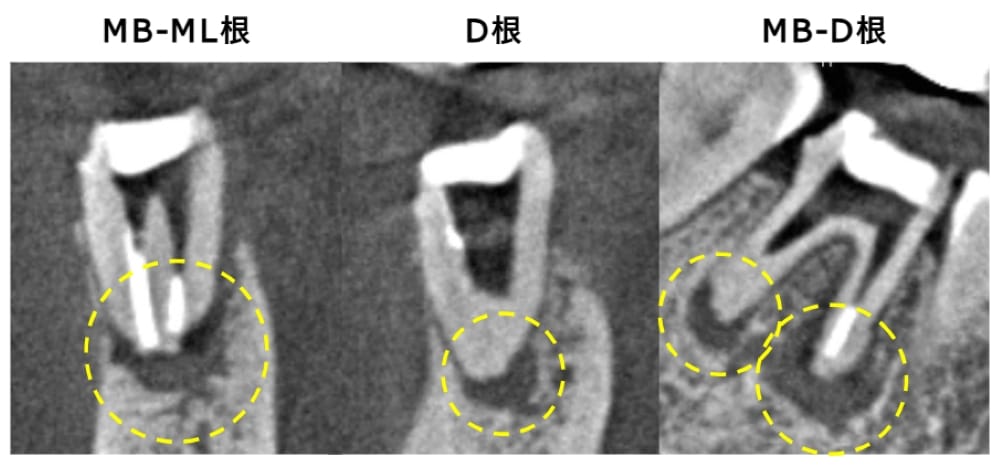

術後6ヶ月が経過時点でのレントゲン・CT画像では、もともとはっきりと写っていた根の先の黒い部分は消失し、骨の回復が認められます。痛みも全くなくなり、治癒していると判断し、最終補綴(かぶせもの)を行うことになりました。